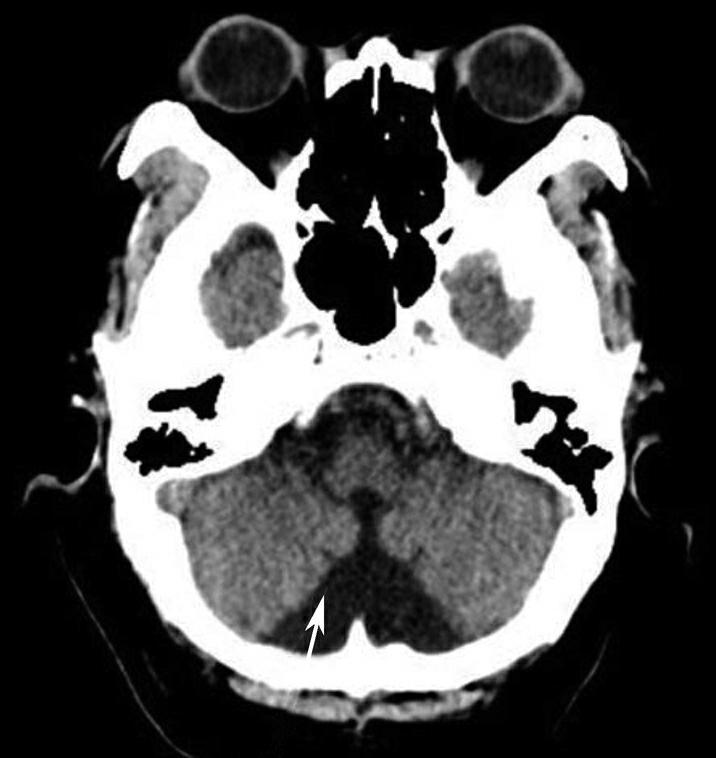

重要结构:鞍上池、视交叉、中脑、环池、外侧裂池(图1-2-15~图1-2-17)。

鞍上池位于层面的中部,多数呈六角星形,其前角连大脑纵裂池、两个前外侧角通外侧裂池、两个后外侧角延续为环池,后角为中脑双侧大脑脚之间的脚间池。鞍上池的六条边为前面的两侧额叶底部、外侧边为颞叶钩回,后两条边为大脑脚。如后方为脑桥,则鞍上池呈五角星形。鞍上池内前部有视交叉、视束及漏斗,两侧有颈内动脉。乳头体位于鞍上池后部中脑前方。鞍上池两侧为颞叶,颞叶内侧前部为杏仁体,杏仁体后方为海马,海马内后方向内突出的脑回为海马旁回,海马外侧可见侧脑室颞角。在颞叶前方通过外侧裂池与额叶相隔。鞍上池后方为中脑、中脑后部的中脑导水管及中脑两侧的环池。

鞍上池是该层面需要重点观察的部位。其形态及密度的改变均提示病变(图1-2-18、图1-2-19),例如鞍上池失去正常五角星或六角星形态、甚至闭塞,或者鞍上池密度升高或不均匀。此外,环池闭塞多见于颅内压严重增高的患者,为诊断脑疝的影像学依据(图1-2-20)。

图1-2-20 环池闭塞

右侧颞叶脑内大血肿(★),产生严重的占位效应,环池受压闭塞(箭),脑疝形成